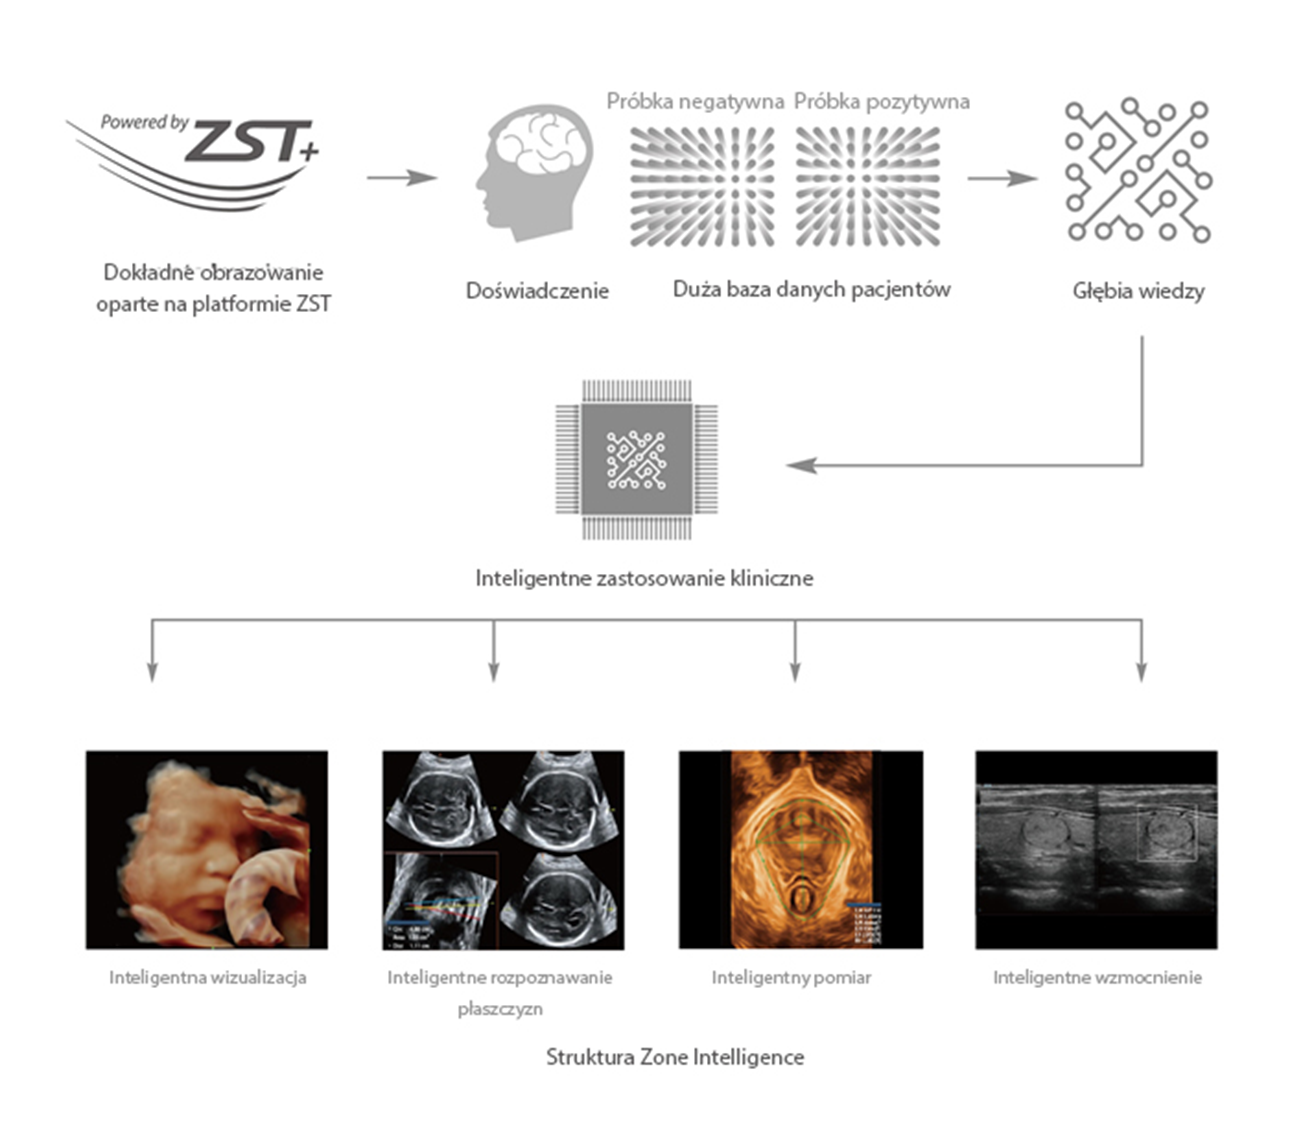

Od czasu kiedy zosta?a za?o?ona, Firma Mindray nieustannie poszukuje nowych sposob├│w na polepszenie precyzji w diagnostyce. Dzi?ki zastosowaniu najbardziej rewolucyjnej technologii ZONE Sonography? Technology, platforma ZST+ zastosowana w aparacie Resona 7 przenosi jako?? obrazu ultrasonograficznego na wy?szy poziom dzi?ki strefowemu uzyskiwaniu obrazu - zone acquisition i obr├│bkce danych kana?owych.

Oprócz uzyskiwania jako?ci obrazu typowego dla aparatów klasy premium, Resona 7 rozszerza mo?liwo?ci klinicznych badań USG dzi?ki rewolucyjnej funkcji V Flow, s?u??cej do oceny hemodynamiki naczyń, a tak?e najlepszej na rynku funkcji inteligentnego, automatycznego uzyskiwania p?aszczyzny na podstawie zestawów danych obj?to?ciowych 3D, umo?liwiaj?cej diagnozowanie stanu Centralnego Uk?adu Nerwowego u p?odu. Aparat Resona 7 ??czy w sobie najbardziej intuicyjn?, wielodotykow? obs?ug? za pomoc? gestów oraz wszystkie kluczowe funkcje kliniczne, co sprawia i? jest prawdziwym liderem we wprowadzaniu innowacji w ultrasonografii.